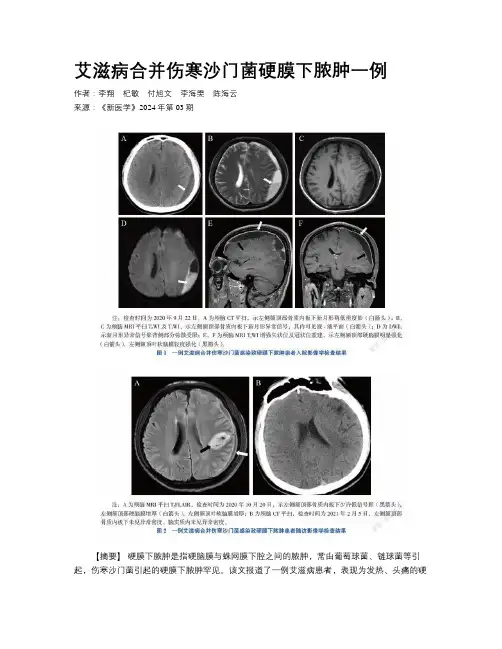

艾滋病合并伤寒沙门菌硬膜下脓肿一例作者:李翔杞敏付旭文李海雯陈海云来源:《新医学》2024年第03期【摘要】硬膜下脓肿是指硬脑膜与蛛网膜下腔之间的脓肿,常由葡萄球菌、链球菌等引起,伤寒沙门菌引起的硬膜下脓肿罕见。

该文报道了一例艾滋病患者,表现为发热、头痛的硬膜下脓肿,血培养、脑脊液高通量测序(NGS)均提示伤寒沙门菌感染,予基于药物敏感试验的敏感抗生素治疗结合外科引流的方法而治愈,引流物培养出伤寒沙门菌。

术后4个月随访,患者症状消失,影像学无异常。

该文提示,伤寒沙门菌引起的颅内感染罕见,可见于免疫功能低下人群,血培养、脓液培养和NGS对于鉴别该病原体感染有重要的价值,确诊后选用敏感抗生素结合外科治疗,可取得良好疗效。